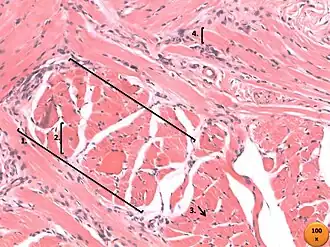

Músculo estriado esquelético de língua. (Hematoxilina-eosina) (HE) 1. Tecido conjuntivo-Perimísio; 2. Tecido conjuntivo-Endomísio; 3. Fibra muscular(transversal); 4. Fibra muscular(longitudinal)

Os músculos estriados esqueléticos são conjuntos de centenas ou milhares de células alongadas, multinucleadas e estriadas.[4] Suas células (miócitos) também chamadas de fibras musculares são agrupadas em feixes envolvidos por uma camada de tecido conjuntivo.[4] Esse tecido é rígido nas extremidades formando os tendões que ligam os músculos aos ossos.[4]

Tanto as fibras como todo o músculo são envolvidos por tecido conjuntivo, que contém os nervos e os vasos sanguíneos.[3] Esses levam oxigênio e nutrientes para as células e retiram o gás carbônico e as substâncias tóxicas resultantes do catabolismo celular, assim como dissipam o calor.[3] A camada do tecido conjuntivo que envolve a fibra muscular é o endomísio.[3] O perimísio é o tecido conjuntivo que envolve um conjunto de feixes de fibras.[3] Por fim, o tecido espesso externo ao músculo é a porção do Epimísio[3]